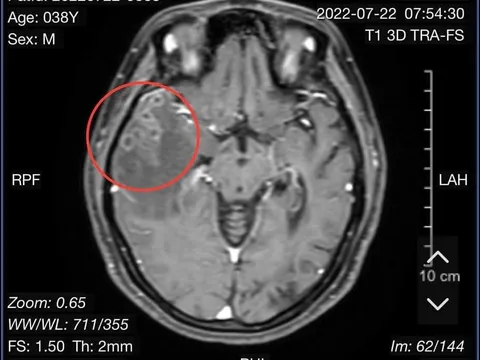

Phát hiện sán cư trú trong não người phụ nữ sau cơn đau đầu

Trước khi vào viện, người bệnh xuất hiện triệu chứng đau đầu dữ dội và có nhiều cơn co giật dù đã kiểm soát bằng thuốc chống động kinh.